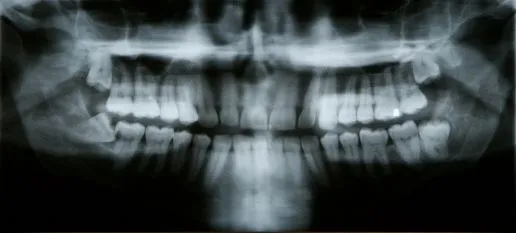

After Impacted Tooth

xray

A tooth becomes impacted when there is not enough room to accommodate the space in the dental arch and growth becomes impossible. After surgery to remove an impacted tooth, mild discomfort and some swelling is expected. This is part of the process and should not alarm you. You may use cold compresses to alleviate the swelling. In addition, your doctor will prescribe pain medication, which should be taken as directed. Patients are also advised to favor the extraction area and modify their diet for a few days to allow for healing.